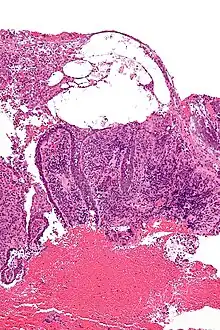

Pemphigus is an autoimmune disease caused by antibodies directed against both desmoglein 1 and desmoglein 3 present in desmosomes. Loss of desmosomes results in loss of cohesion between keratinocytes in the epidermis, and a disruption of the barrier function served by intact skin. The process is classified as a type II hypersensitivity reaction (in which antibodies bind to antigens on the body's own tissues). On histology, the basal keratinocytes are usually still attached to the basement membrane leading to a characteristic appearance called "tombstoning". Transudative fluid accumulates in between the keratinocytes and the basal layer (suprabasal split), forming a blister and resulting in what is known as a positive Nikolsky's sign. This is a contrasting feature from bullous pemphigoid, which is thought to be due to anti-hemidesmosome antibodies, and where the detachment occurs between the epidermis and dermis (subepidermal bullae). Clinically, pemphigus vulgaris is characterized by extensive flaccid blisters and mucocutaneous erosions. The severity of the disease, as well as the mucosal lesions, is believed to be directly proportional to the levels of desmoglein 3. Milder forms of pemphigus (like foliacious and erythematoses) are more anti-desmoglein 1 heavy.

Because it is a rare disease, diagnosis is often complicated and takes a long time. Early in the disease patients may have erosions in the mouth or blisters on the skin. These blisters can be itchy or painful. Theoretically, the blisters should demonstrate a positive Nikolsky's sign, in which the skin sloughs off from slight rubbing, but this is not always reliable. The gold standard for diagnosis is a punch biopsy from the area around the lesion that is examined by direct immunofluorescent staining, in which cells are acantholytic, that is, lacking the normal intercellular connections that hold them together. These can also be seen on a Tzanck smear. These cells are basically rounded, nucleated keratinocytes formed due to antibody mediated damage to cell adhesion protein desmoglein.